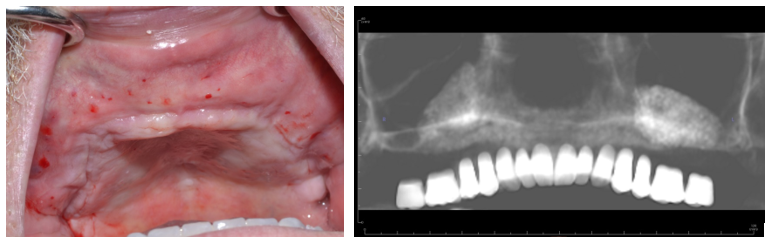

Figure 1a. Photo demonstrating Class V ridge after flap elevation. This was a 38-year-old female, who demonstrated significant atrophy in the buccal-lingual dimension. The vertical height was also insufficient for implant placement.

Figure 1b. Completion of bilateral sinus lift dissection. Note elevation of full palatal flap. This is necessary to relieve tension on the wound closure in addition to labial and buccal full muco-periosteal reflection as high as the infraorbital rims. The periosteum is then scored to allow flap mobilization. The sinus lifts were performed in the standard fashion.

Figure 1. 67-year-old male with class VI ridge and pneumatized sinuses with 1mm residual ridge height. Bilateral sinus lifts with ridge augmentation were performed with a tissue engineering approach utilizing bone marrow aspirate concentrate (BMAC) and rBMP-2.

Figure 2a. 3-D model reconstructed from preoperative conebeam ct scan revealing severe atrophy down to the nasal floor.